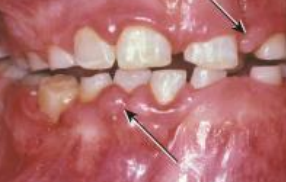

Papillon-Lefèvre Syndrome GENE: cathepsin C gene 手掌與腳底

• Cathepsin C: 溶酶體內蛋白酶

• 手掌與腳底的角質化

• 皮膚病灶的治療:維 A 酸類(systemic retinoids)

• PMN 功能不足 → 嚴重牙周病

• 快速的骨流失 → floating in air

• 瀰漫出血與增生性牙齦炎